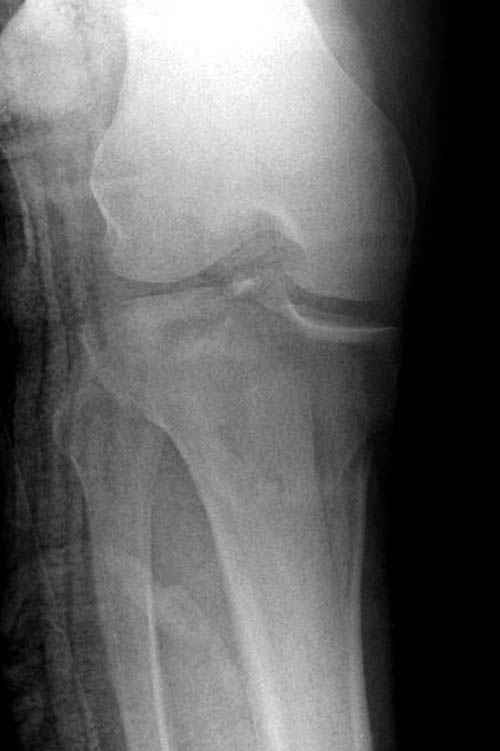

Пациенту сделали КТ - ухитрились сделать на шине Белера (не давал положить прямую ногу) - срезали передний отдел. Планируется на пятницу (24.12) на операцию - синтез длинной мыщелковой LCP-пластиной Synthes :). Отек ближе к слову умеренный (окружность голени +4 см по сравнению со здоровой). КТ и снимок на вытяжении прилагаются.

Трудно поверить, что разрекламированная Ортопедическая школа Восточной Украины позволяет такие странные снимки? На прямом снимке сохранен общий контур плато, но не известна судьба импрессии суставной поверхности. На полубоковой?, оставлен без репозиции задне-медиальный отдел, и навряд ли после такой фиксации можно удовлетвориться результатом.

Здесь как раз тот случай, когда результат зависит не только от мастерства хирурга, но и от наличия современных методов исследования. Например, КТ которая поможет рассчитать направления шурупов и установку импланта. Кроме этого, поможет определиться с доступом.